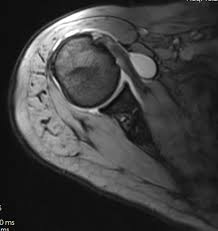

An upright mri allows patients to be scanned while standing or sitting, which can be helpful in diagnosing certain conditions. Does it seem you have no choice in where you go and what you pay for a radiology procedure? Private physios, paying for mri scans & torn shoulder problems. Estimate the cost of your mri or ct scan at american health imaging with our simple calculator. However, there are also alternatives such as ultrasound, which can also confirm rotator cuff tears.

Estimate the cost of your mri or ct scan at american health imaging with our simple calculator. $800 pesos ($43.24 usd) mri of lumbar spine without dye: Super angebote für mri procedure hier im preisvergleich. Rotator cuff tears can often be diagnosed by physical examination, but cannot be confirmed without imaging. A mri in salt lake city costs $890 on average when you take the median of the 17 medical providers who perform mri procedures in salt lake city, ut. Average prices are for mri procedures performed at honorhealth facilities around the valley, and do not include physicians' fees. When i called one facility, they told me the mri i described would cost $1,600. In different conditions, the cost for even just one mri scan can surpass $13,000. They can range from $300 to $9000. Mri spine cervical w/o cont. I went to my gp after about 6 weeks of shoulder pain who said i'd torn something in my shoulder & referred me to physio, who i saw today. Please contact your physician's office and health insurance provider directly for price information. Our experienced staff are friendly and approachable, and can answer any.

Estimate the cost of your mri or ct scan at american health imaging with our simple calculator. Please contact your physician's office and health insurance provider directly for price information. How much does an mri cost? If patients have not hit their deductible, that money comes straight. Surgeries / operations (head & torso) The cost of an mri will vary greatly between inpatientand outpatient facilities. How much does an mri cost? Those on high deductible health plans or without insurance can save when they buy their procedure upfront through mdsave. Although they may not say so, some physicians in health care systems or hospital groups are contracted with hospitals. If a person receives an mri scan at the. Our experienced staff are friendly and approachable, and can answer any. A shoulder mri is done to check a shoulder for arthritis, bone tumors, torn ligaments or tendons, and other similar problems. Read more about how mdsave works.